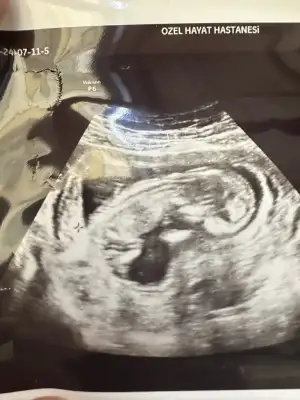

Benimkinede bakabilirmisiniz rica etsem

• IMG_20240710_115629.webp

IMG_20240710_115629.webp

27,9 KB · Görüntüleme: 69